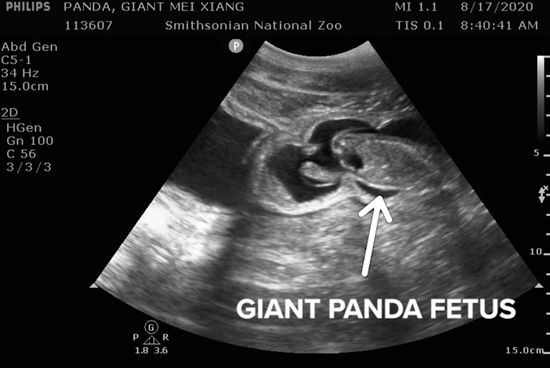

8月14日,动物园按捺不住,为美香作了一次b超检查。兽医们发现,在只有黑白两色的超声波图像中,一个幼小的身影在羊水中踢腿、游泳,它的脊椎和血流清晰可见。

美香的产检b超影像(来源:美国国家动物园)